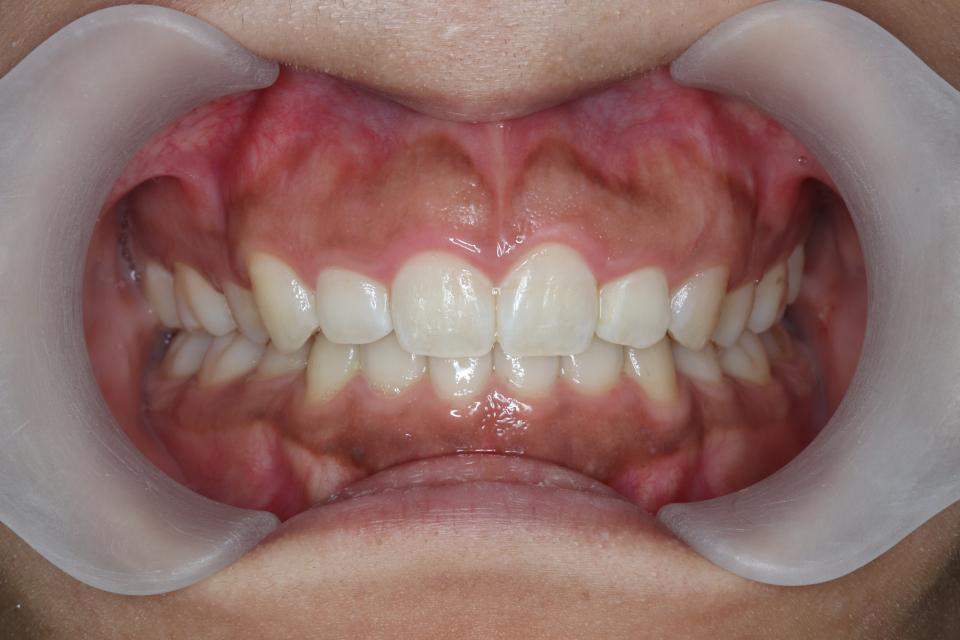

矯正治療後

30代女性の患者さんです。

前歯の歯並びが気になり来院されました。

マウスピース型の矯正治療装置を使用し、前歯の歯並びのみの改善を行いました。

現在は保定装置を使用し定期的にチェックしています。